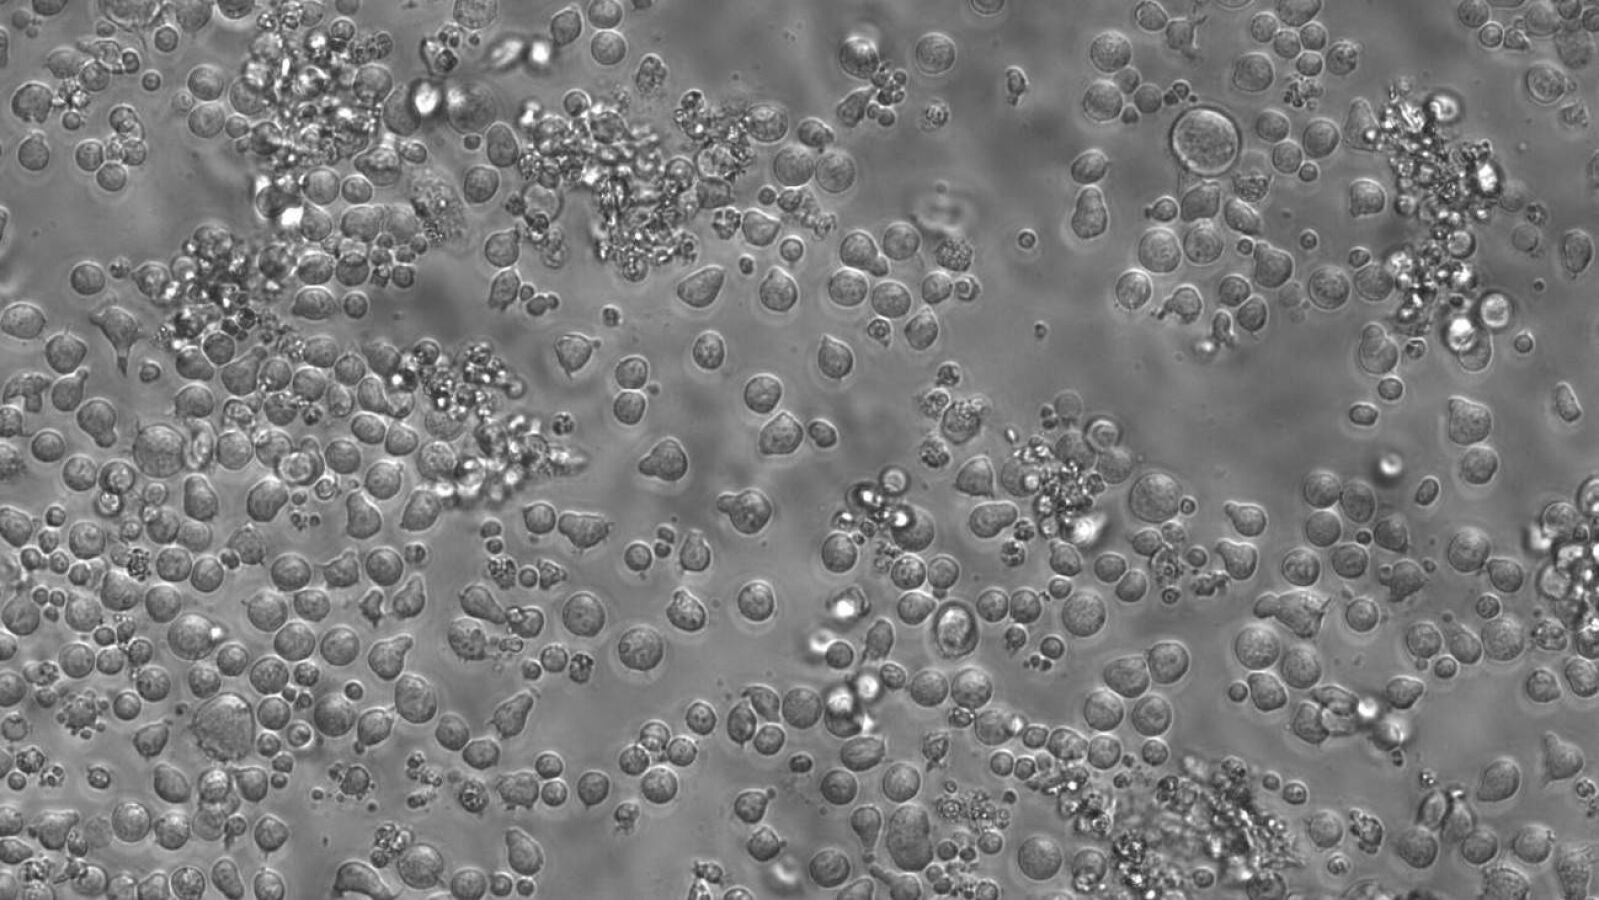

Con el paso de los años, el sistema sanguíneo envejece y se degrada debido a que la competencia entre las células madre que lo componen se desequilibra. Esto altera la producción de nuevas células sanguíneas y aumenta la posibilidad de sufrir enfermedades.

Un nuevo estudio, publicado en Nature, consigue rastrear en humanos cada una de estas células hasta su progenitora original, lo que ha permitido observar cambios en las marcas químicas adheridas al ADN — metilaciones — que indican qué genes se activan o silencian.

En sus estudios con ratones, se dieron cuenta de que mientras la sangre joven contaba con miles de células madre diferentes que contribuían a la creación de partículas necesarias para el organismo, en la de especímenes de edad avanzada el 70% de las células madre pertenecían a la misma familia.

La situación era parecida en los humanos, aunque el porcentaje exacto variaba entre una docena de donantes sanos, entre 35 y 70 años, que participaron en el estudio. Los que tenían más de 50 años contaban con menos diversidad de células.